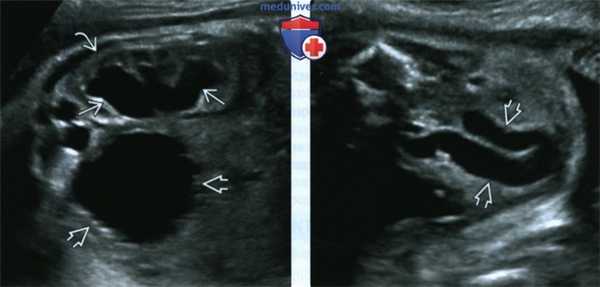

(Слева) УЗИ плода в III триместре. КЗУ. Выраженный гидронефроз и истончение почечной паренхимы. Стенка мочевого пузыря утолщена и покрыта трабекулами. Эти признаки характерны для обструкции выходного отверстия мочевого пузыря вследствие КЗУ.

(Справа) Тот же случай. Отличить гидроуретер от петель кишечника в III триместре можно по отсутствию перистальтики и взвеси в просвете. Информативно также продольное сканирование мочеточника в режиме реального времени.

2. УЗИ при клапанах задней уретры у плода:

• Мужской пол плода:

• Перерастяжение мочевого пузыря:

о Расширенная задняя уретра принимает форму замочной скважины:

о Толстые стенки с выступающими трабекулами:

• Гидронефроз, гидроуретер различной степени:

о Расширенные на всем протяжении мочеточники имеют вид петель кишечника